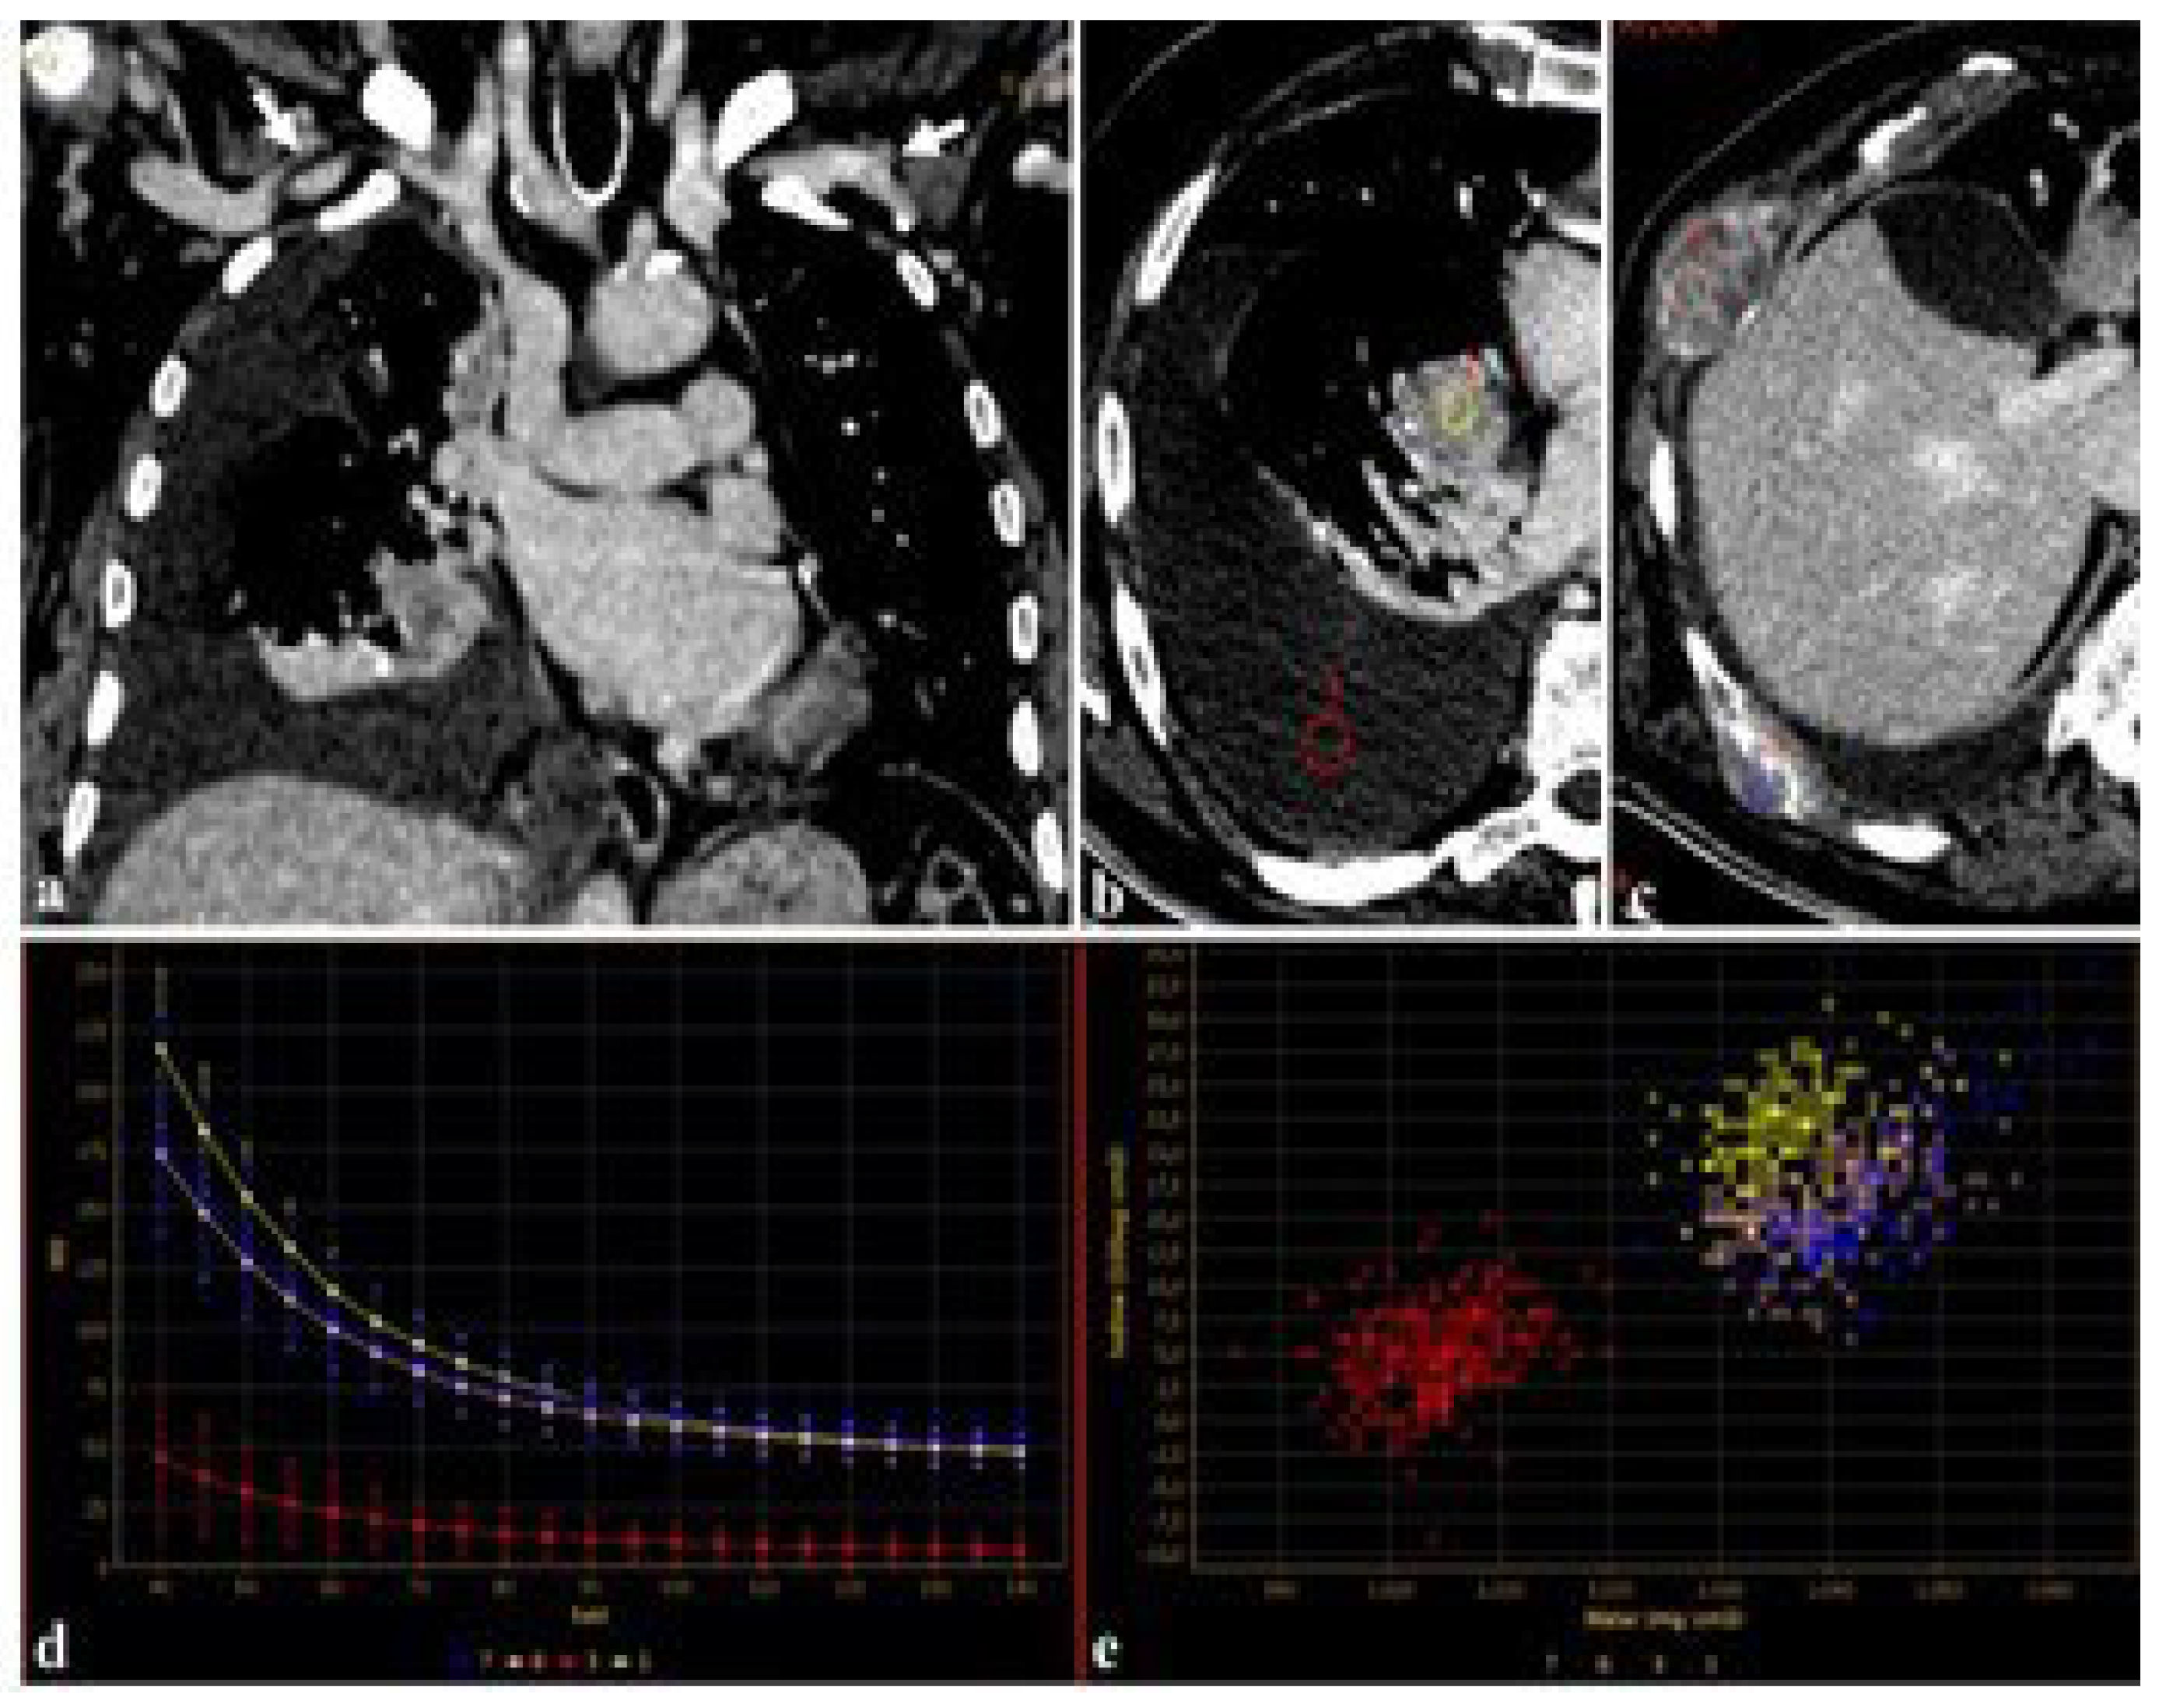

Furthermore, using DECT, the attenuation of iodine for a given region of interest (ROI) can be represented as a spectral curve representing the change in attenuation values and iodine uptake in different ROIs [35]. These spectral curves can be used in the evaluation of primary and secondary lesions, regardless of the amount of CM employed (Figure 3).

Figure 3.

An 83-year-old male candidate for transcatheter aortic valve implantation (TAVI) submitted to DECT examination. The study of the thoracoabdominal aorta (a), performed with 85 mL of contrast media for the evaluation of peripheral accesses ((a), arrows), revealed a pulmonary right hilar cancer (b) with osteolytic bone metastases (c). After drawing circular regions of interest (ROIs) within right hilar mass, pleural effusion (b), and bone metastases (c), the attenuation was measured at the given energy level, demonstrating the absence of disease in the pleural effusion (b,d,e), further confirmed by spectral iodine maps ((d), spectral curve, (e), scatterplot GSI).